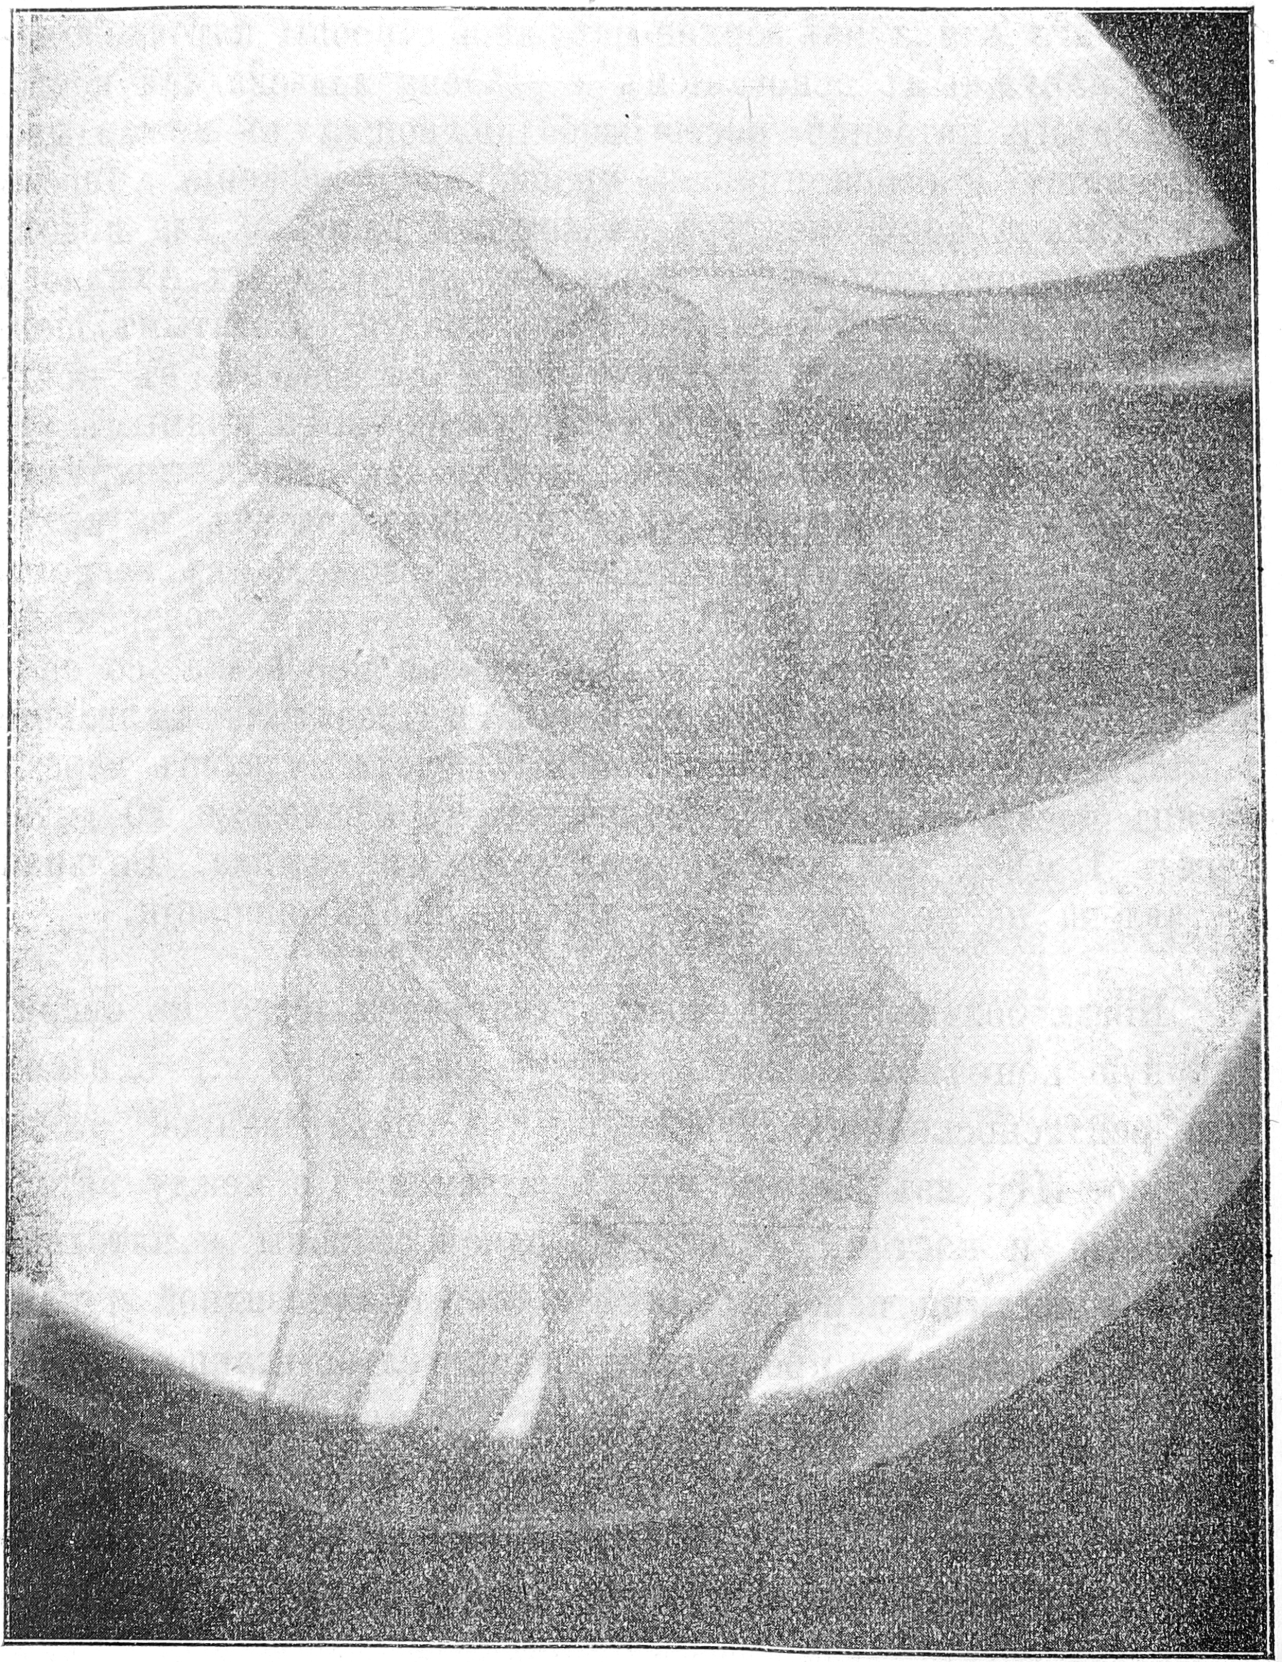

Status praesens. Больная слабаго тѣлосложенія, съ атрофированной подкожной клѣтчаткой и мускулатурой, особенно нижнихъ и верхнихъ конечностей. Со стороны внутреннихъ органовъ отклоненій отъ нормы не замѣчается. Рѣзкія измѣненія находимъ въ стопахъ. Прежде всего обращаетъ на себя вниманіе (см. рис. 1) рѣзкое приведеніе обѣихъ стопъ кнутри, образующихъ съ голенью уголъ, равный 80—85° и расположенныхъ такимъ образомъ, что верхушки стопъ обращены къ средней линіи.

Рис. I.

Далѣе, стопы повернуты около своей оси внутрь такъ, что подошвы (при стояніи больной) обращены всей своей поверхностью вверхъ, тылъ же стопъ всей своей наружной половиной соприкасается съ воломъ, служа плоскостью опоры при стояніи и ходьбѣ, и представляется покрытымъ мозолисто-утолщеннымъ эпидермисомъ въ области наружной части таранной, пяточной и кубовидной костей. Края стопъ изогнуты: внутренніе вогнуты и смотрятъ при стояніи впередъ и вверхъ, наружные выпуклы и расположены внизъ и назадъ. Большіе пальцы согнуты въ видѣ крючковъ и лежатъ въ одной фронтальной плоскости. Кромѣ того, стопы находятся въ сильномъ подошвенномъ сгибаніи, при чемъ замѣчается рѣзко выраженная поперечная складка на углубленной подошвѣ стопъ; тылъ же стопъ представляется очень выпуклымъ. Блокъ таранной кости смѣщенъ впередъ и кнаружи, головка ея хорошо прощупывается; кубовидная и пяточная кости сильно выдаются на наружномъ краѣ стопъ. Кромѣ того, наблюдается рѣзкое поднятіе пятки; высшая точка ея находится на одномъ уровнѣ съ мыщелками. Внутренній мыщелокъ едва прощупывается, наружный рѣзко выдается. Внѣ стоянія положеніе стопъ почти не измѣняется. Измѣненія обѣихъ стопъ представляются одинаковыми. Активныя движенія въ голено-таранномъ сочлененіи утрачены, пассивныя движенія рѣзко ограничены. Ходитъ больная съ большимъ трудомъ, опираясь на палку. Замѣчается рѣзкая атрофія мышцъ голени, доходящая почти до полнаго исчезновенія ихъ. Измѣненія со стороны нервно мышечнаго аппарата уже извѣстны изъ сообщенія д-ра Первушина (см. протоколъ VII очереднаго засѣданія Об—ва невроп. и психіатровъ, Невролог. Вѣсти. т. XVI вып. I г. 1909). Укажемъ лишь, что въ данномъ случаѣ не обнаруживается реакціи перерожденія и измѣненія чувствительности при параличѣ и паретическомъ состояніи мышцъ стопъ, голеней, кистей и предплечій и послѣдовательной рѣзкой атрофіи ихъ. Рентгеновскій снимокъ, сдѣланный съ правой ноги (см. рис. II), обнаруживаетъ слѣдующее: весь блокъ таранной кости смѣщенъ впередъ и кнаружи (subluxatio tabi), пятка находится на уровнѣ лодыжекъ, наружная лодыжка приближена къ пяточному бугру, рѣзко выражена, тогда какъ внутренняя лодыжка отстаетъ въ своемъ развитіи и почти отсутствуетъ.